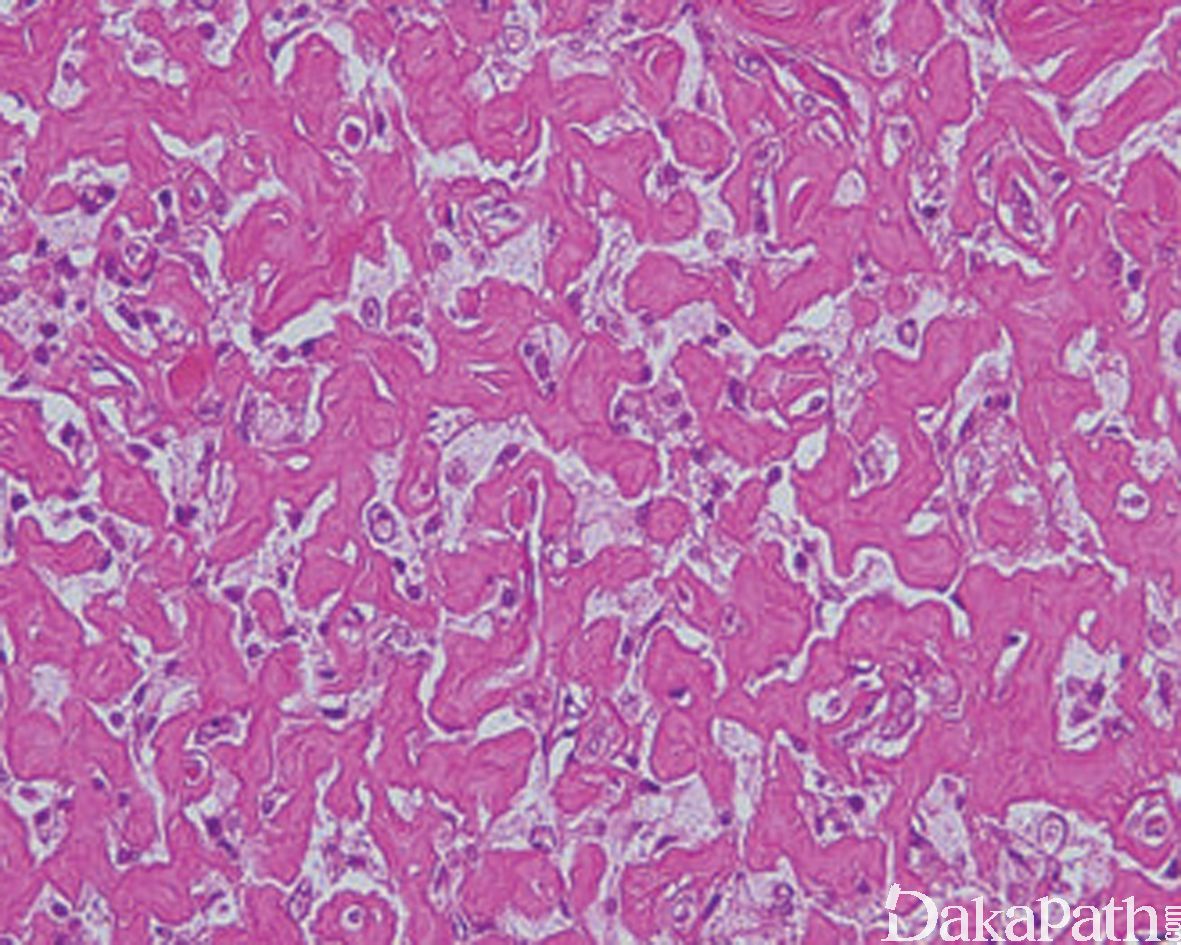

镜下见局灶典型的良性纤维组织细胞瘤的背景中多量的瘤细胞呈现丰富的泡沫样胞浆;

间质呈玻璃样变性,似疤痕疙瘩样或骨样机制样。